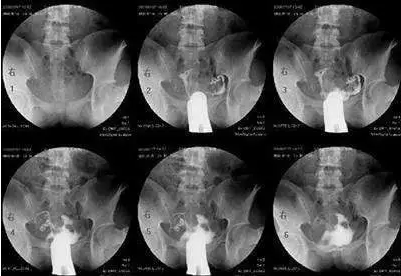

當然,以上說的都是可能性的癥狀,并不代表有這些癥狀就一定是輸卵管有問題的。如果有這些癥狀,要適度警惕一下。當然,您也不需要太擔憂,最好還要結合多種情況綜合考慮,如果實在不放心,可以去醫院做做輸卵管造影術,或者做輸卵管通水、腹腔鏡檢查、輸卵管鏡檢查等。

最常用的是輸卵管碘油造影(HSG)

醫生會根據不孕的時間、可能的原因,來選擇是否需要做造影。

造影的時間一般在月經干凈后3天到排卵之前,造影前不要有性生活,白帶檢查正常等等。造影后1周禁性生活,當月最好不要嘗試懷孕。

不過現在的造影劑比較先進,一般代謝很快,假如不小心當月懷上,多數也沒有問題。保險一點,等下次月經來過再試孕。